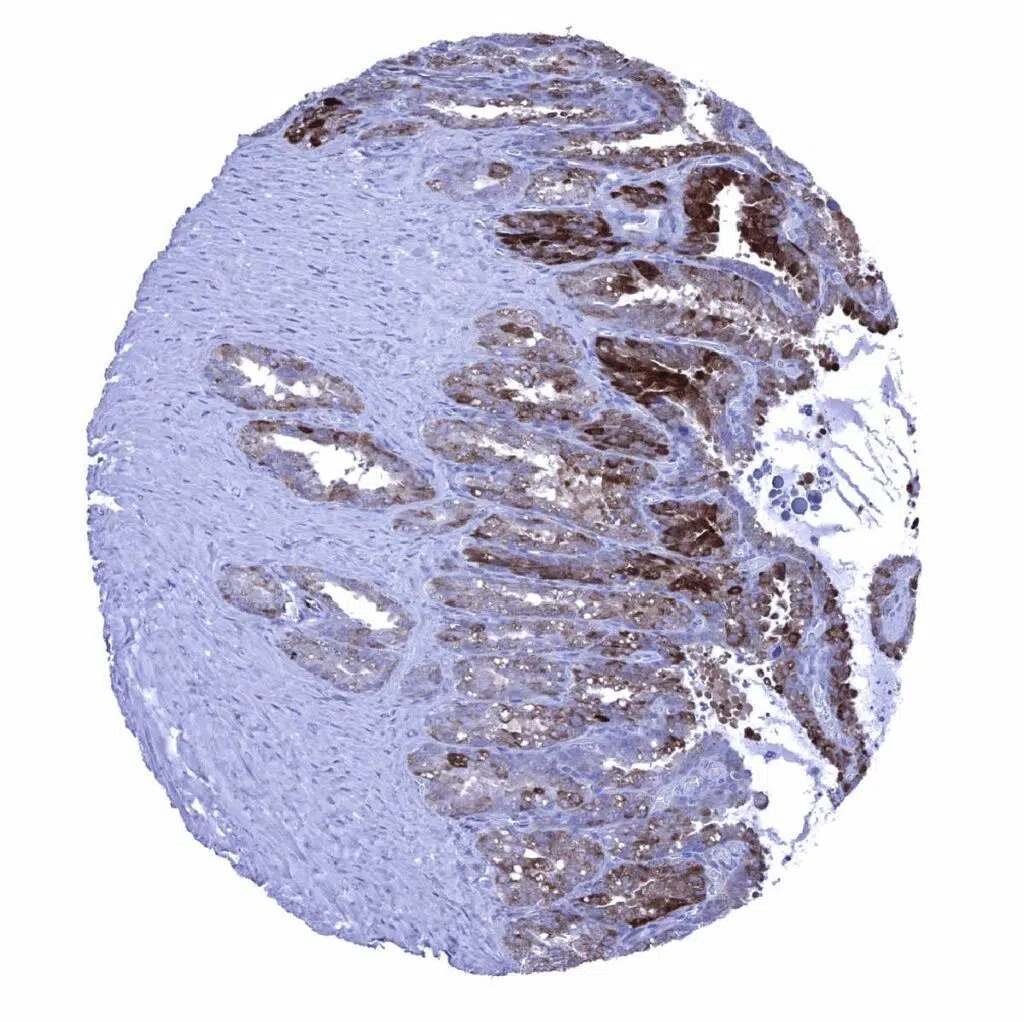

Stomach, corpus – A strong GS staining is seen in glandular cells while staining is only weak in surface epithelial cells